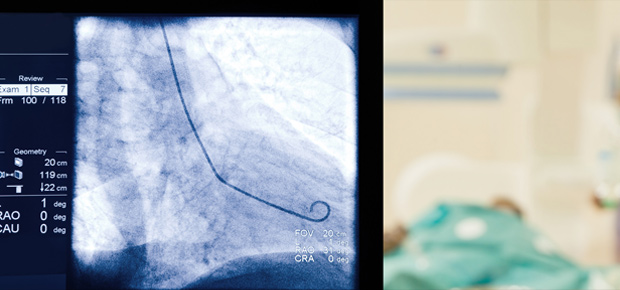

Cateterismo Cardíaco – Cineangiocoronariografia (Realização no H. S. Filomena)

Trata-se de exame invasivo, porém de avaliação direta da anatomia cardíaca. É utilizado para diagnóstico de doenças coronárias e outras enfermidades do coração, tais como cardiopatias congênitas e doenças valvares. O exame é realizado através de técnicas de punção da artéria femoral, na região inguinal, ou artéria radial, ao nível do punho, por onde se passa um cateter alcançando-se a aorta até sua origem onde nascem as coronárias (artérias que irrigam o coração). Faz-se então injeção de contraste radiopaco (isto é, visível com uso do raio X) permitindo o estudo detalhado das coronárias, válvulas e cavidades cardíacas. Na doença coronária é possível se identificar pontos de afilamento da passagem do contraste pelo vaso que denotam a presença de obstruções (deposição de placas), precursoras do infarto. O tratamento pode ser realizado em casos individualizados através da angioplastia coronária com implante de stent. A realização de USOM intra-coronário e medidas de fluxo coronário, por meio do cateterismo, podem auxiliar na avaliação e na indicação do melhor tratamento.